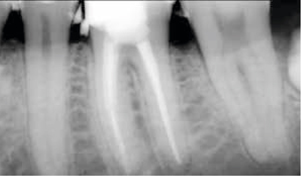

Afb. 9-10

Solo-opnamen van het 1e en 3e kwadrant.

Röntgenonderzoek

Röntgenologisch onderzoek laat meerdere problemen zien. Onder andere een forse zwarting apicaal van element 12 met het beeld passend bij periapicale problematiek en een verleden van apicale chirurgie (afbeelding 8-12 ).